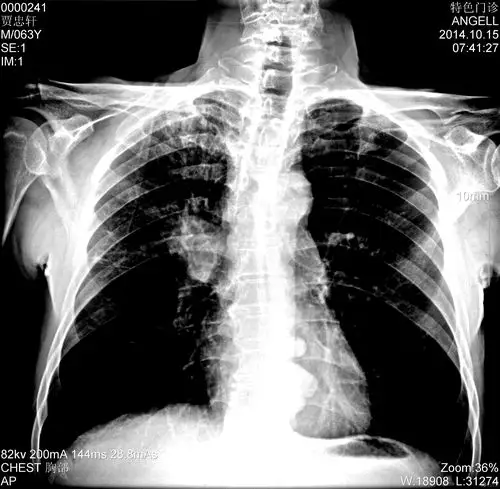

临床医师胸部x线诊断

典型的肺癌

(图) 大细胞中分化型肺癌